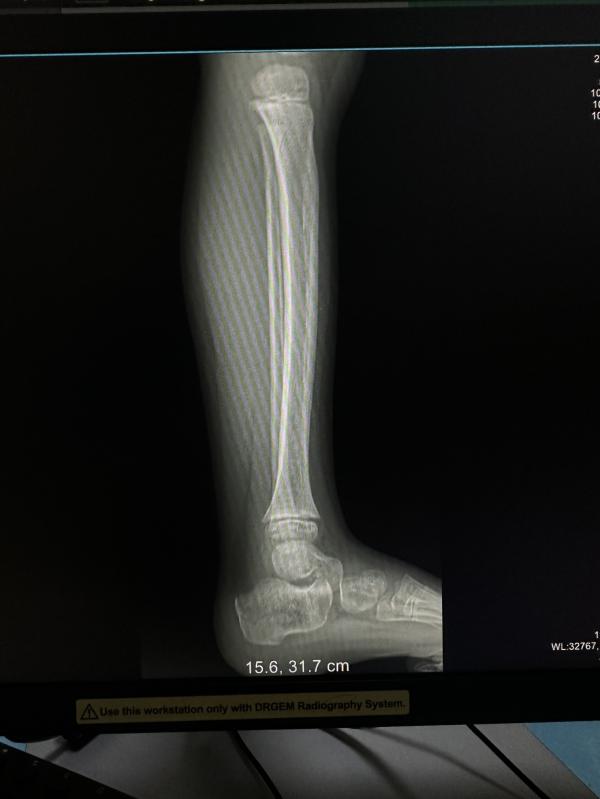

Старшый сын упал с турников,точнее спрыгнул неудачно.

Травматолог ничего не назначил. Ушиб.

Но ребенок не ходит. Передвигается на четвереньках.

А ходить больно говорит.